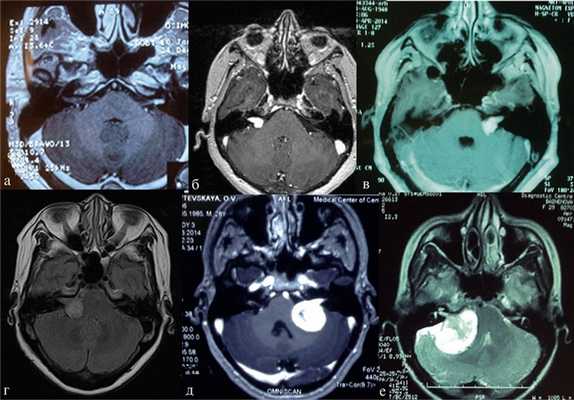

Более точно установить диагноз «невринома слухового нерва» помогает рентгенография и методы нейровизуализации. На ранних стадиях при малых размерах невриномы (до 1 см) она, как правило, не визуализируется при помощи КТ головного мозга. Поэтому проводят рентгенографию черепа с прицельным снимком височной кости. В подтверждение диагноза вестибулярной шванномы свидетельствует расширение внутреннего слухового прохода. Поскольку невриномы хорошо поглощают контраст, возможно использование КТ с контрастированием. При этом визуализируется образование с четкими гладкими контурами.

МРТ головного мозга в случае невриномы выявляет на Т1-взвешенных снимках гипо- или изоинтенсивное, а на Т2-взвешенных - гиперинтенсивное образование. Для опухолей размером 3 и более см характерна гетерогенность сигнала, связанная с наличием в них кистозных участков. Возможна визуализация деформации ствола мозга и мозжечка. При проведении контрастной МР-томографии в 70% наблюдается гетерогенное накопление контраста.